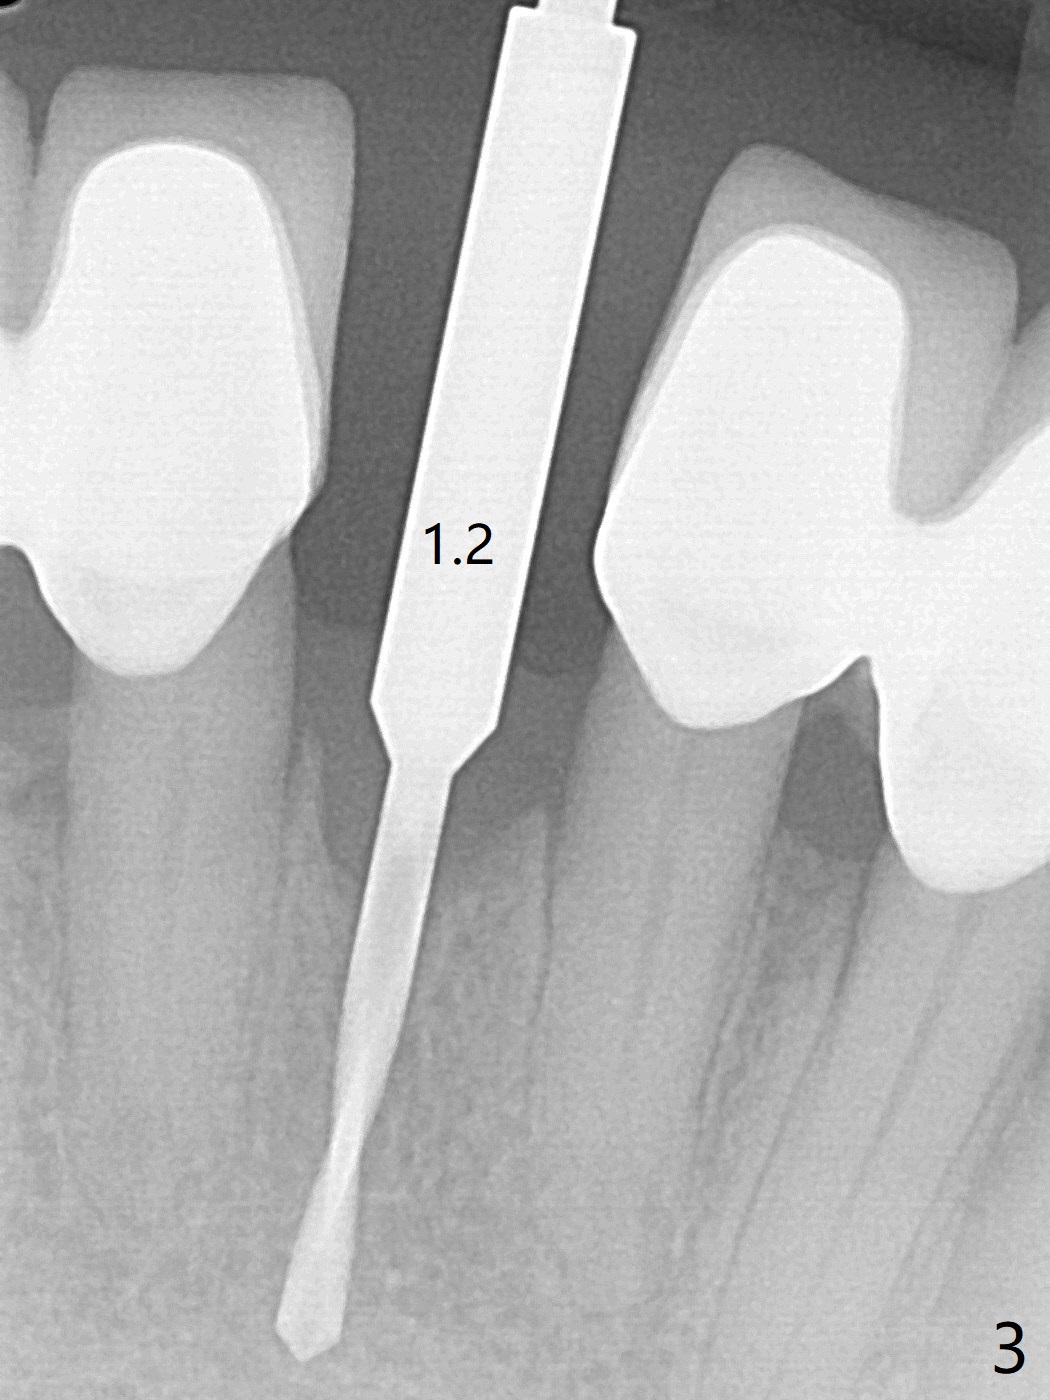

种植前与66岁女病人再次讨论下前牙正中种植可能产生不对称问题,她好像不在乎。术前检查显示下前牙正中间隙偏左(图一),处理似乎容易,但是牙槽嵴相当狭窄(图一 *,二 箭头)。牙槽嵴切除后(大约3 毫米宽(颊舌侧)),初期钻洞似乎偏移右边(图三),矫正后(图四),植入2乘10(4)毫米连体植体(图五,比预计小,因为骨质薄),放置骨粉(图五,六 *)和膜,缝合,制作即刻修复物(图七 T),病人满意,牙槽骨饱满了。术后一个多月临时牙冠取出修正,伤口愈合,由于植骨颊侧没有凹陷(图八),而舌侧隆起(图九:*,与图二术前对比)。其实病人不小心吃牛肉时损伤植体,疼痛几天。尽管最近吃饭时植牙又受伤,但是没有松动,也没有骨质吸收,就是局部结石多(图十,术后四个月)。正式牙冠术后4.5个月粘固(图十一)。